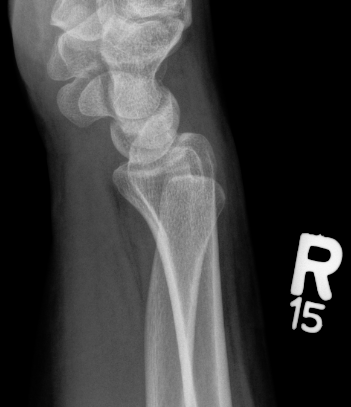

Galeazzi fracture

Galeazzi fracture with DRUJ disruption

Incidence of DRUJ instability after radius ORIF

Rettig et al J Hand Surg Am 2001

- 40 patients with Galeazzi fracture dislocations

- DRUJ instability after radius ORIF

- Type 1: radius fracture < 7.5 cm to articular surface: 55% DRUJ instability

- TYpe II: radius fracture > 7.5 cm to articular surface: 6% DRUJ instability